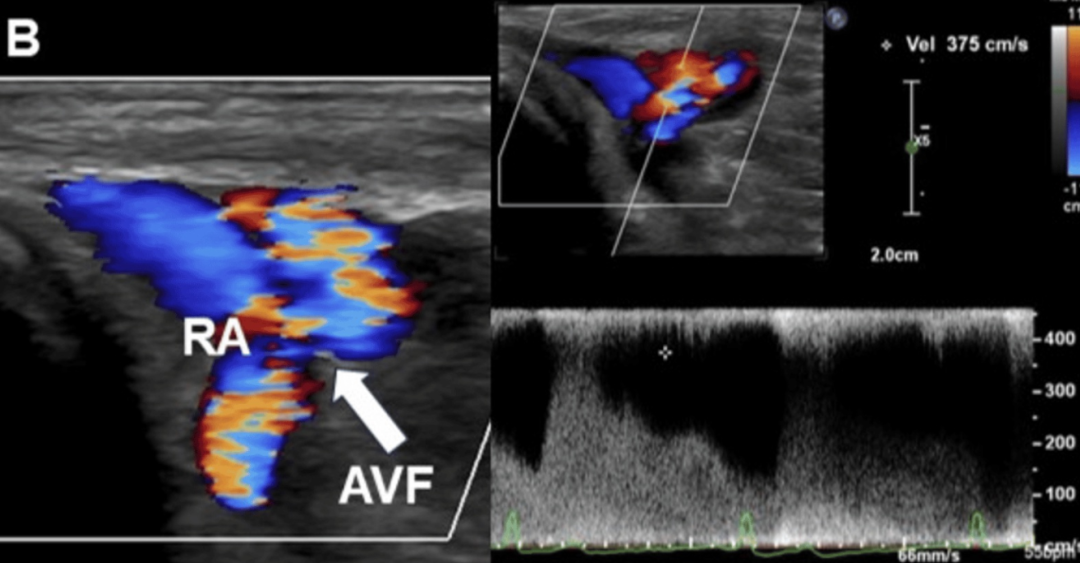

图1.dTRA形成动静脉瘘的照片、超声表现和血管造影图像。

(A)观察到扩张的头静脉。(B)箭头显示动静脉瘘的入口,即桡动脉与静脉连接处。浅表超声检查发现远端桡动脉有一个直径为2.0mm、流速为3.75m/s的动静脉瘘。(C)桡动脉造影。显示远端桡动脉与手背静脉网之间存在分流,并且头静脉和贵要静脉显影。分流位于桡动脉至靠近拇指掌骨的静脉处。(D)常见的远端桡动脉穿刺部位(三角形)和本例的穿刺部位(星形)。

超声检查在穿刺部位发现了一个动静脉瘘(AVF)。分流处的最大流速为3.75m/s,瘘口直径为2.0mm(图1B,视频1)。

箭头显示动静脉瘘的入口,即桡动脉与静脉连接处。